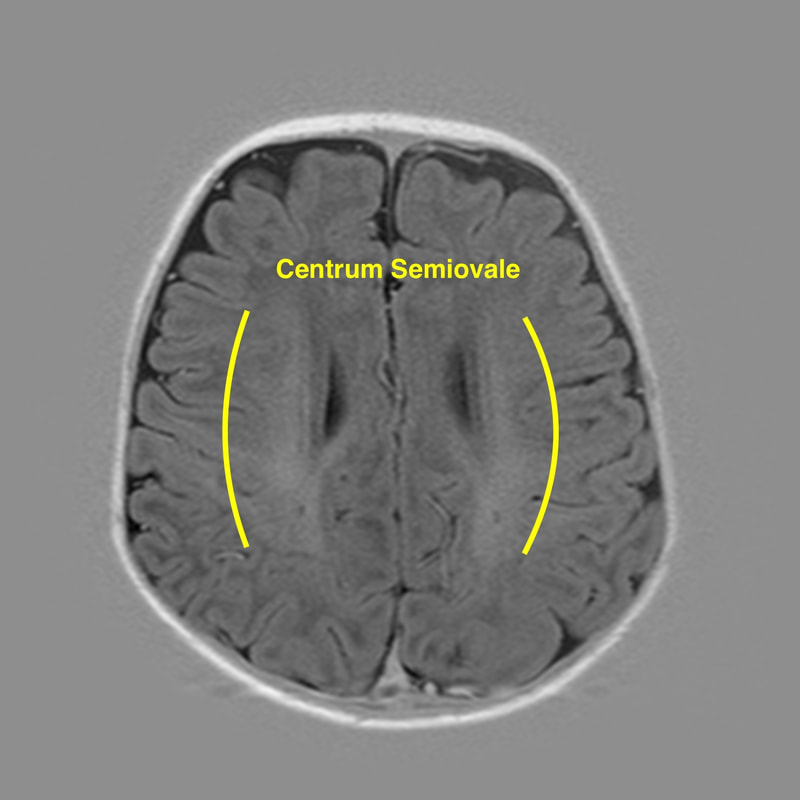

The centrum semiovale (plural: centra semiovale) is a paired mass of white matter superior to the lateral ventricles and corpus callosum, present in each of the cerebral hemispheres, subjacent to the cerebral cortex.

It has a semi-oval shape and contains projection, commissural, and association fibers, with a newly formed tumor on the left side causing stroke often.